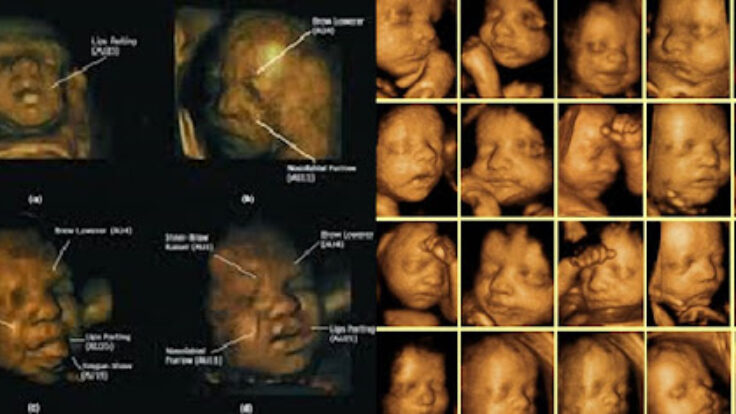

4 Boyutlu ultrason tamamen eş zamanlı olarak uzaysal görünümün ekrana yansımasını sağlayan en son teknolojik üründür. 3 boyutlu görüntünün aynı zamanda kaydedilebilir özelliği nedeniyle 4 boyutlu ultrason olarak adlandırılır. 4 boyut özelliği olan tüm cihazlarda bebeğin iki boyutlu görüntüleri ve ölçümleri yapılabilmektedir.

Özellikle gebelik takibinde kullandığımız ultrason cihazlarının 2 boyutlu bebeği görüntülemesi ve ölçümler, gebeliğin tüm haftalarında olmazsa olmaz muayenemizdir. 4D özelliği olan cihazların 2 boyutlu görüntüleme kalitesi, geleneksel 2 boyutlu cihazlara göre çok üstündür. Ayrıca 4 boyutlu ultrasonların renkli doppler özelliği de mevcuttur. İlk haftalarda bebeğin oluşumu, kalp atımı, bebeğin ölçümü, ileri haftalarda organ taramaları, fetal büyümenin ve tahmini ağırlığın tespiti 2 boyutlu ölçümlerle yapılır. Ancak fetal organ taramalarında 4D inceleme önemli bir yer tutar. Yarık damak, yarık dudak, yüz anomalileri, bebeğin sırtında ve karın duvarında olabilecek anomalilerin tespitinde yardımcıdır. 4D ultrasonda bebeğin hareketlerini izlemek, esnediğini, parmak emdiğini, ellerini, bacaklarını görmek, ileri haftalarda kime benzediğine dair gözlemleme, heyecanla bebeğini bekleyen çiftleri çok mutlu eder. Ayrıca görüntülerin kayıt altına alınması, evde yakınlarla izlemek oldukça keyiflidir.